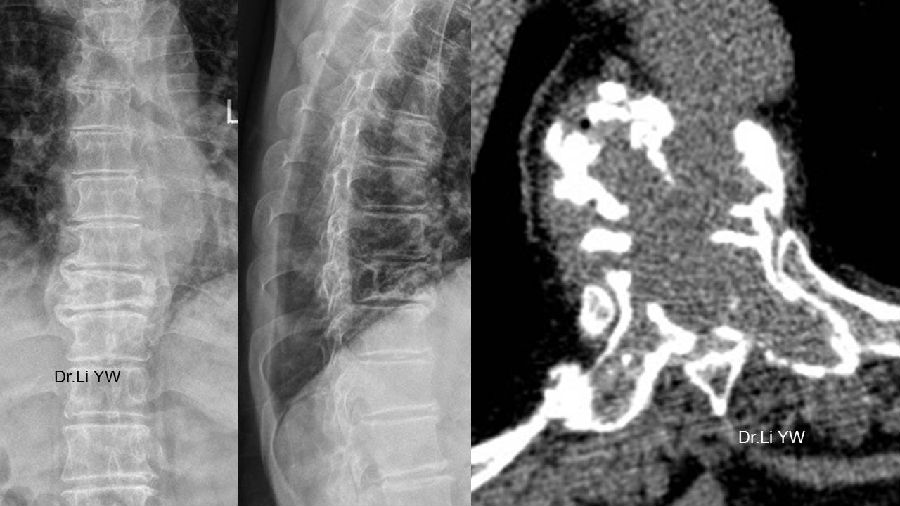

(五)3D打印人工椎体的临床应用

达到了与椎体界面严丝合缝。

3D打印人工颈椎置换术,被腾讯新闻报道,学术论文发表在中华创伤骨科杂志。

临床效果优良。